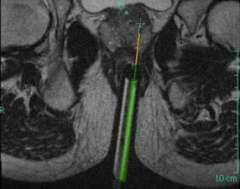

LEFT: Oblique Axial T2-weighted image from in-bore MR-guided targeting

RIGHT: Corresponding sagittal T2-weighted image from in-bore MR-guided targeting